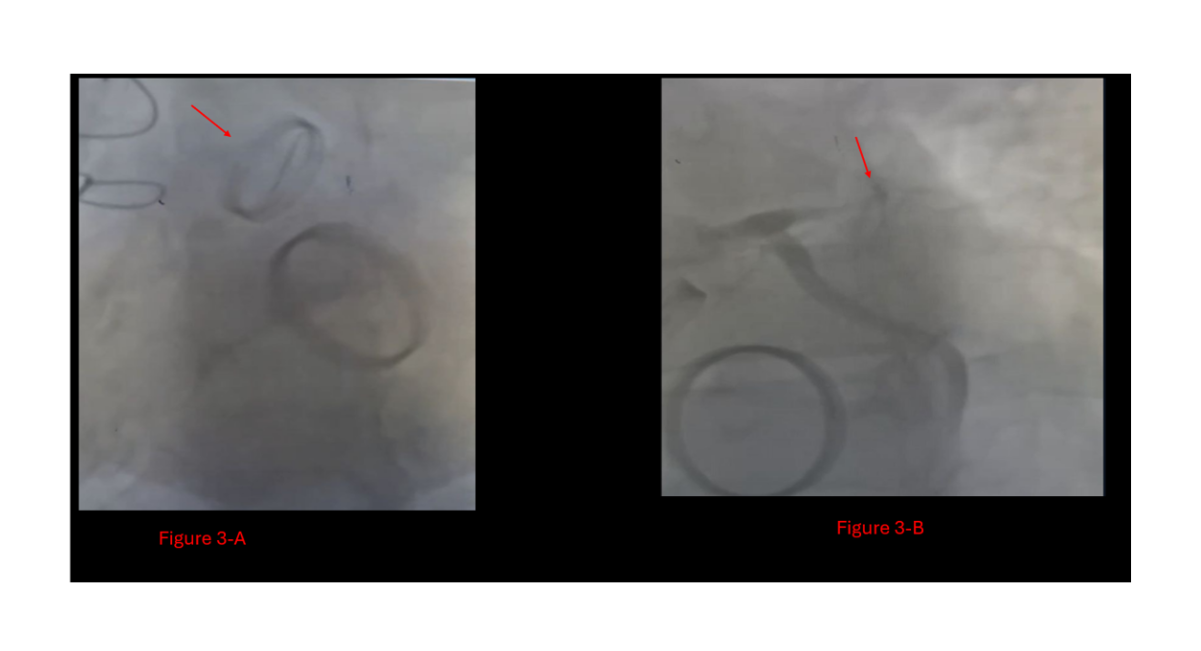

A 50-year-old male with a history of hypertension and double mechanical valve replacement five years ago, maintained on chronic warfarin therapy, presented to the emergency department with typical symptoms of acute myocardial infarction (MI). On arrival, he was hemodynamically unstable, with a blood pressure of 90/60 mmHg and a heart rate of 70 bpm. Routine MI workup, including ECG (Figure 1), revealed an isolated anterior ST-elevation MI (STEMI). Following standard guidelines, an echocardiogram was performed and demonstrated a severely elevated aortic valve gradient of 60 mmHg, suggestive of severe aortic stenosis (Figure 2). The INR was pending at that time. Urgent diagnostic coronary angiography via the radial approach was conducted. Fluoroscopy revealed a stuck mechanical aortic valve: one leaflet was completely immobile, while the other one was partially restricted. Additionally, a thrombus was visualized in the proximal part of the left anterior descending (LAD) artery. It was presumed that thrombus formation on the aortic valve had embolized during diastole into the LAD (Figure 3, video 1).

Figure 3: The fluoroscopy of the patient's admission,

A: Stuck prosthetic aortic valve with only one leaflet movement,

B: Total LAD occlusion by the proximal thrombus